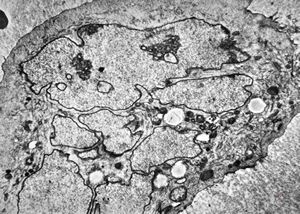

bone marrow … plasmocytoma (parafin-embedded sample)